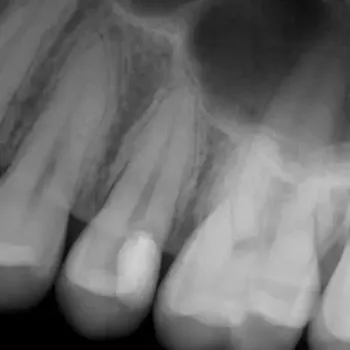

Fall 3: Obliterierte Kanäle

Ausgangssituation

Kontrolle nach Wurzelfüllung